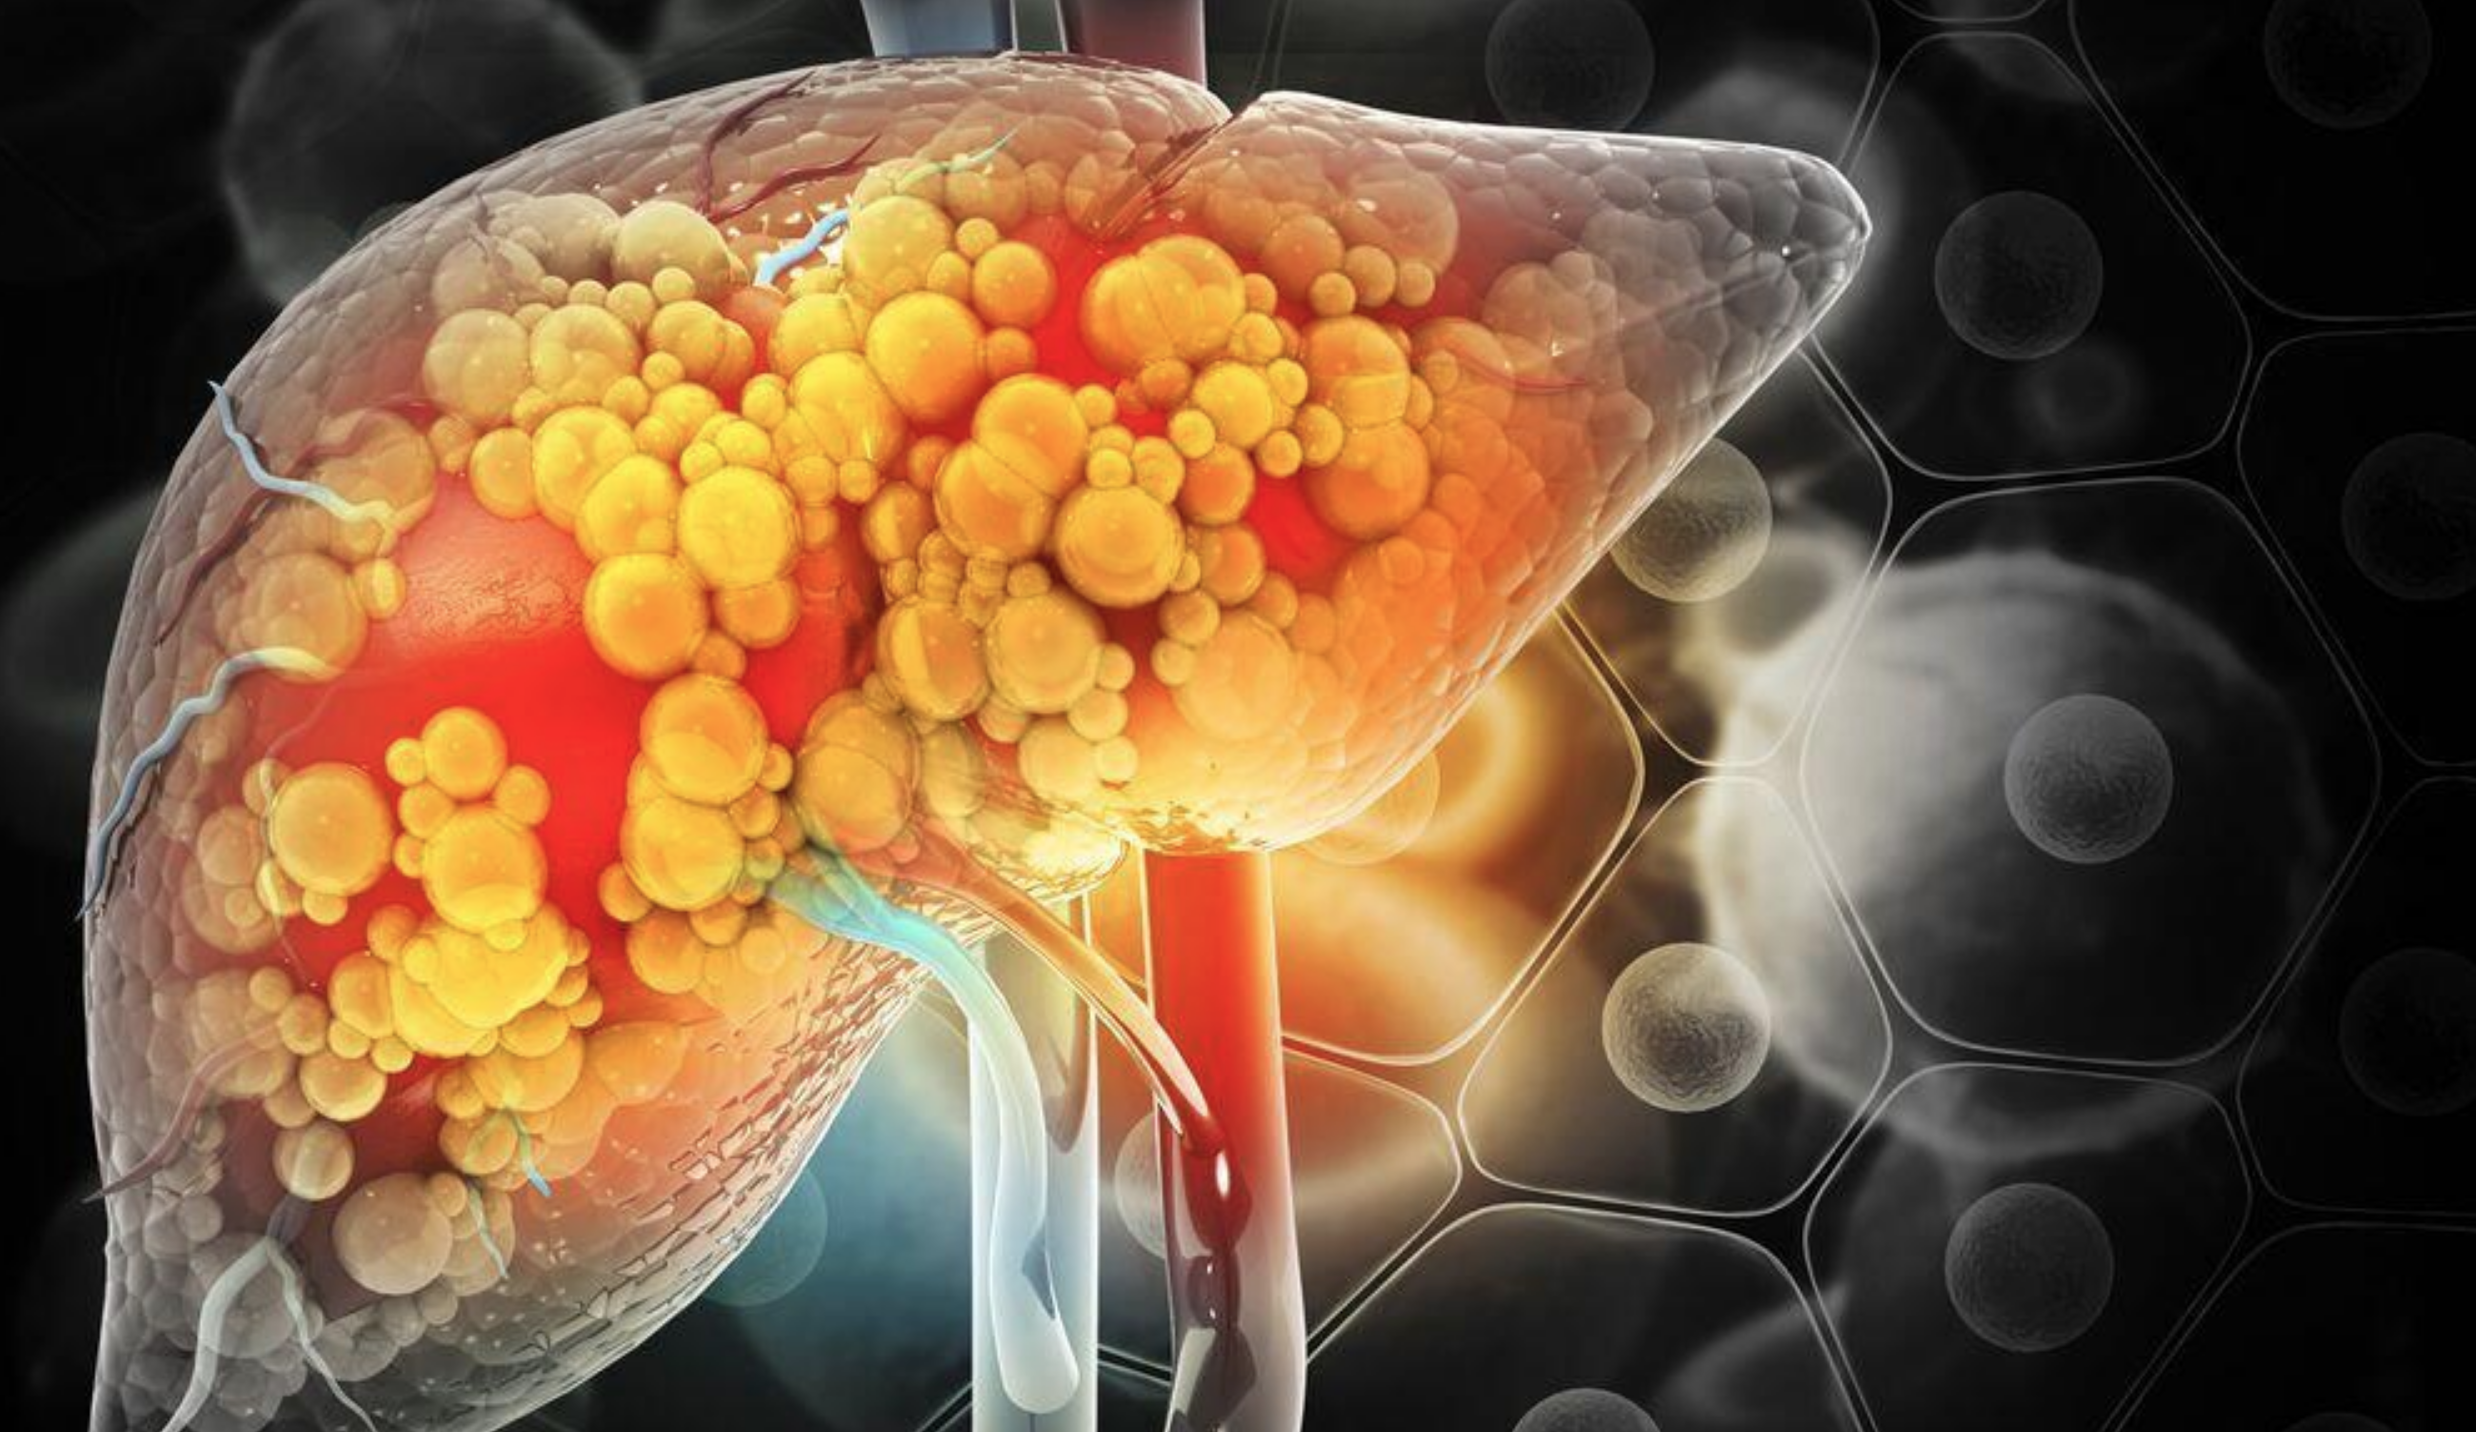

El hígado graso metabólico, conocido como MASLD por sus siglas en inglés, se ha convertido en uno de los principales problemas de salud pública en México. Se estima que cerca de la mitad de los adultos presenta algún grado de acumulación de grasa en el hígado relacionada con alteraciones metabólicas, como resistencia a la insulina, niveles elevados de triglicéridos, presión arterial alta u obesidad.

El hígado es un órgano fundamental que metaboliza nutrientes, depura sustancias tóxicas, sintetiza proteínas y regula procesos clave del organismo.

Sin embargo, cuando empieza a acumular grasa y a inflamarse, no envía señales de alarma. “El hígado no duele. Puede pasar una década sin que la persona lo note”, explica la Asociación Mexicana de Hepatología.

Por ello, la falta de síntomas es uno de los mayores riesgos: muchos pacientes reciben el diagnóstico cuando la enfermedad ya avanzó hacia fibrosis o cirrosis.

Entre las causas destacan predisposición genética debido a variantes del gen PNPLA3, resistencia a la insulina más frecuente y factores socioeconómicos que dificultan el acceso a atención médica oportuna. A esto se suma un estilo de vida cada vez más sedentario, dietas con exceso de harinas refinadas, alimentos ultraprocesados, azúcares y consumo regular de alcohol.

Aunque suele asociarse al sobrepeso, el MASLD también afecta a personas con peso normal. La mala calidad del sueño, el nivel de estrés y una alimentación desordenada también pueden detonarlo.

La buena noticia es que la enfermedad es reversible en etapas tempranas. Ajustes en la dieta, reducción o eliminación del consumo de alcohol, aumento de actividad física y controles médicos periódicos son claves para frenar su progresión. Los especialistas recomiendan realizar estudios de laboratorio y ultrasonido incluso en ausencia de síntomas, especialmente en personas con factores de riesgo metabólico.